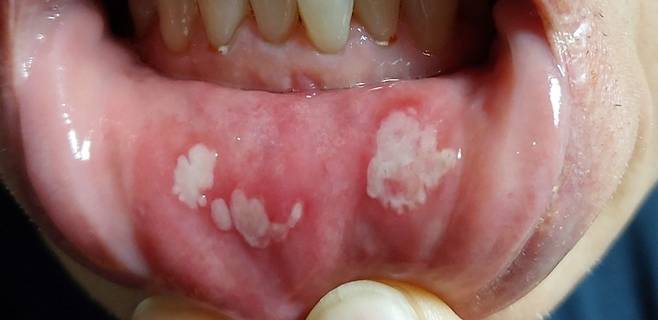

국내 유명 쇼핑몰 후기에서도 이갈이 방지를 위해 셀프 마우스피스를 구매했던 소비자들이 ‘치은 부종’ 등 여러 부작용을 겪고 있는 사례가 확인됐다. 셀프 이갈이 방지 장치를 구매해 2주간 사용했다는 A씨는 “양치는 물론 음식 먹기도 고통스럽다”는 후기를 남겼다. 협회는 “사진 상 구강 내에 점막 궤양이 유발된 것으로 보인다”고 밝혔다.